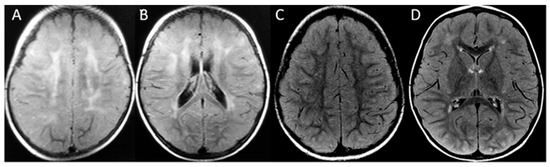

| Image Modality | Patient | 1 | 2 | 3 | 4 | 5 | 6 |

|---|---|---|---|---|---|---|---|

| Distribution | Diffuse/homogeneous | Patchy/asymmetric | Patchy/asymmetric | Patchy/asymmetric | Patchy/asymmetric | Patchy/asymmetric | |

| MRI at onset | Predominant location | Diffuse | Frontal and anterior temporal | Frontal and anterior temporal | Frontal and anterior temporal | Frontal and anterior temporal | Frontal and parietal |

| Infratentorial involvement | Pons | - | - | - | - | Pons | |

| Contrast enhancement | + | - | - | - | - | - | |

| MRI at follow up | Months after onset | 1st episode 8 mo (2 y 3 mo old) | |||||

| 2nd episode | |||||||

| 12 mo | 4 y | 10 mo | 24 mo | 13 y | 5 mo | ||

| (6 years old) | (6 years old) | (2 y 2 mo old) | (3 y 2 mo old) | (13 years old) | (20 mo old) | ||

| WM lesions improvement | Marked | Marked | Marked | Marked | Marked | Marked | |

| Brain Atrophy | Mild | - | Mild | - | - | - | |

| CT scan | Time after onset | 5 y | 4 y | 7 y | 1 mo | 13 y | 2 mo |

| Calcification | - | - | - | Basal ganglia | - | - |